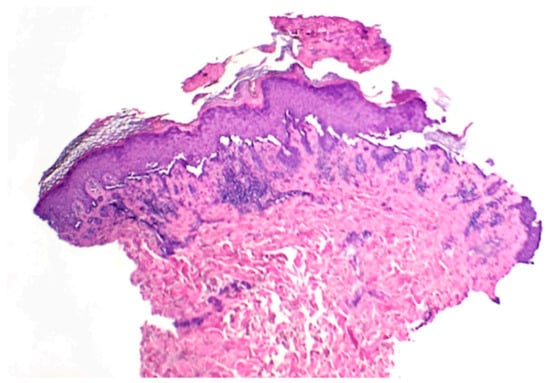

A Rare Case of Transient Acantholytic Dermatosis (AKA. Grover’s Disease) with Concomitant Pediculosis Pubis: An Atypical Presentation and First Documented Case Report

- Lacarrubba, F.; Boscaglia, S.; Nasca, M.R.; Caltabiano, R.; Micali, G. Grover’s disease: Dermoscopy, reflectance confocal microscopy and histopathological correlation. Dermatol. Pract. Concept. 2017, 7, 51–54. [Google Scholar] [CrossRef] [PubMed]